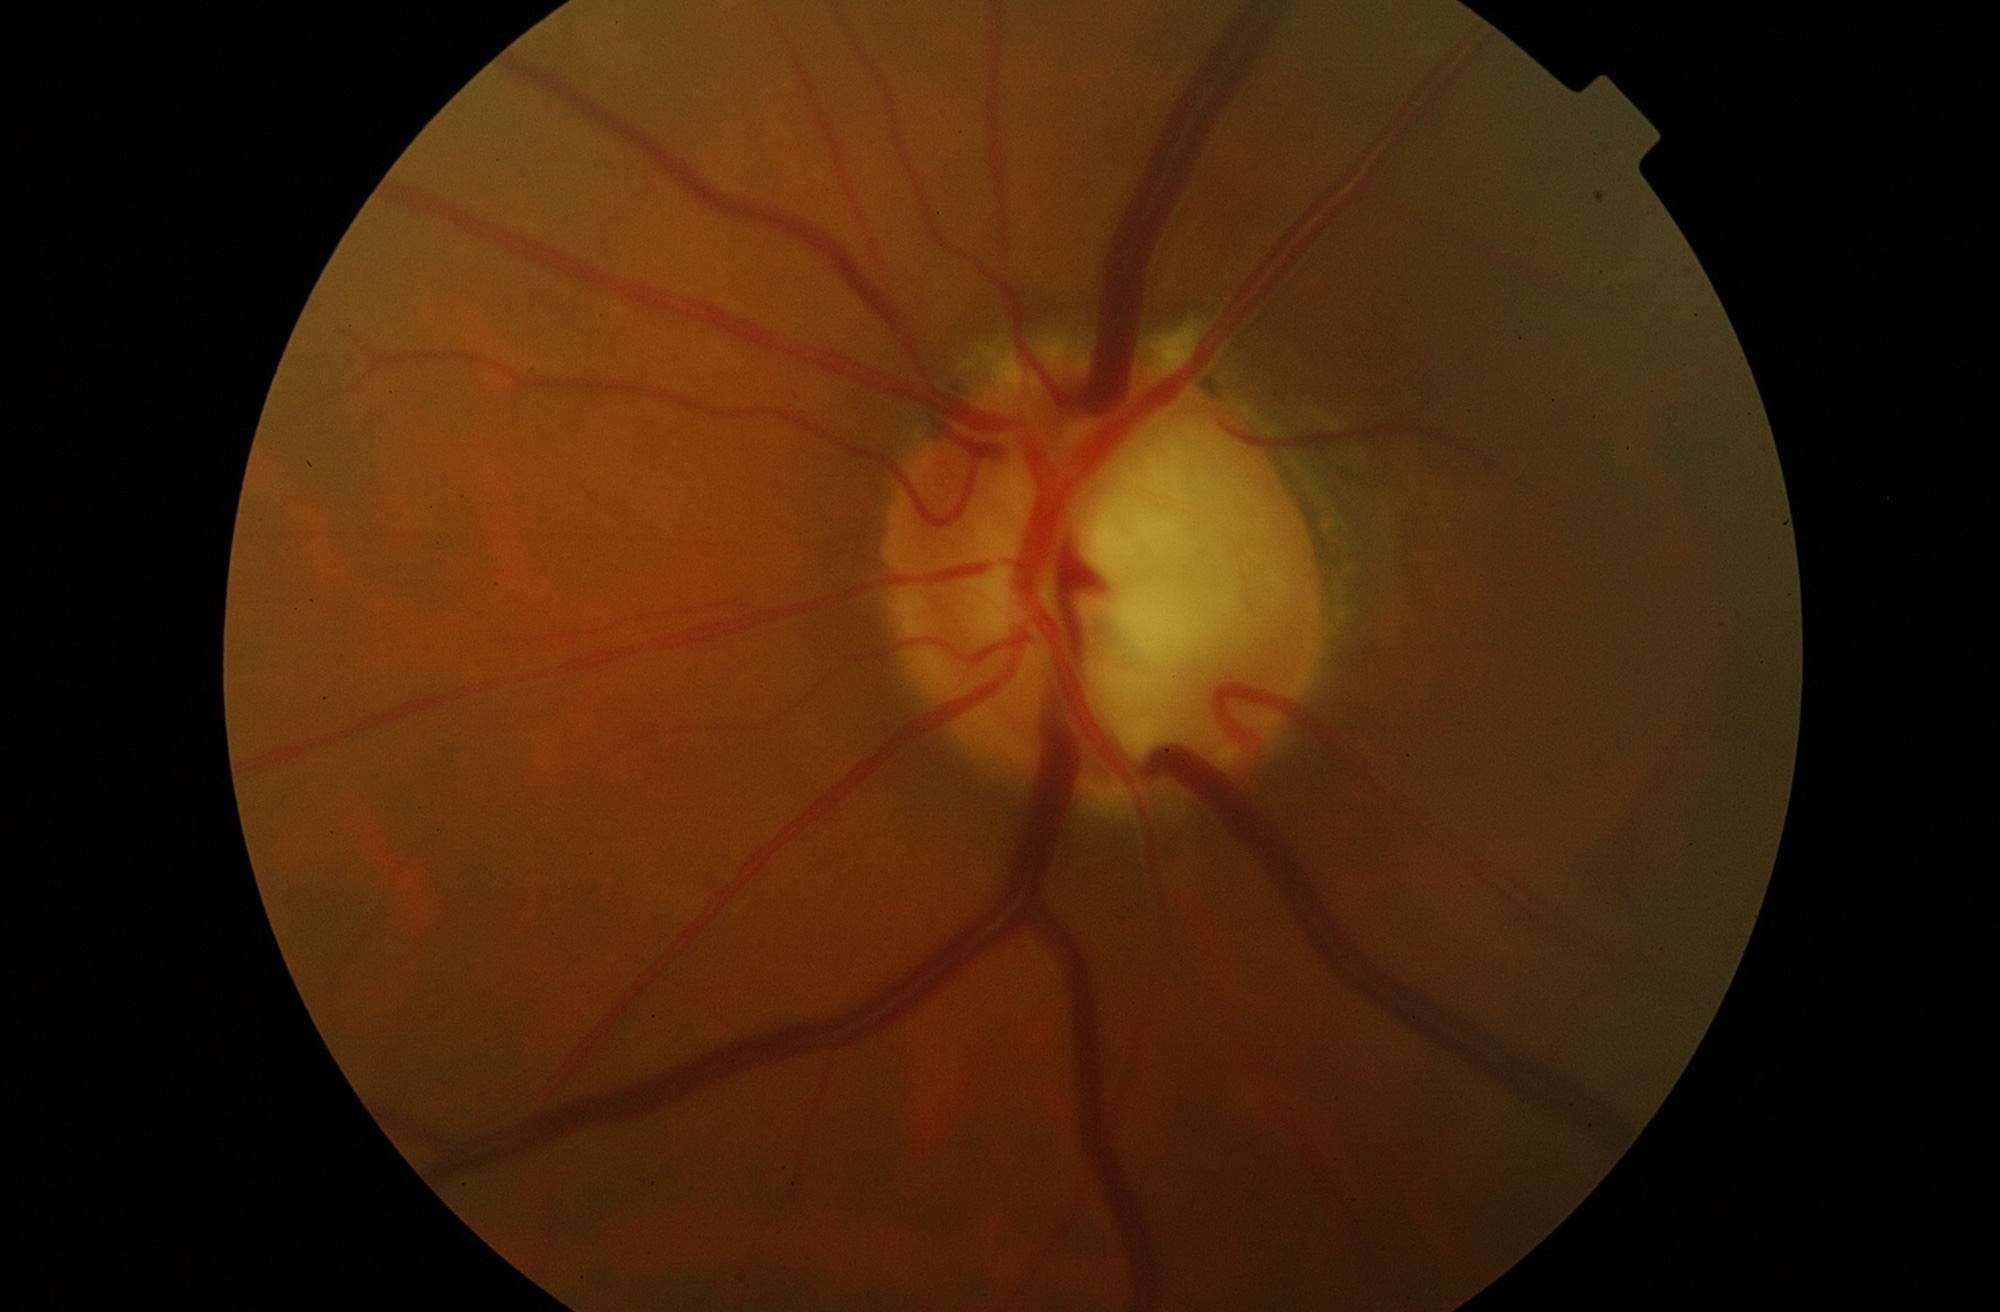

Glaucoma Crónico

Es una enfermedad que daña las fibras del nervio óptico (neuropatía) dándole un aspecto característico y se acompaña por una alteración de la visión lenta pero irreversible.